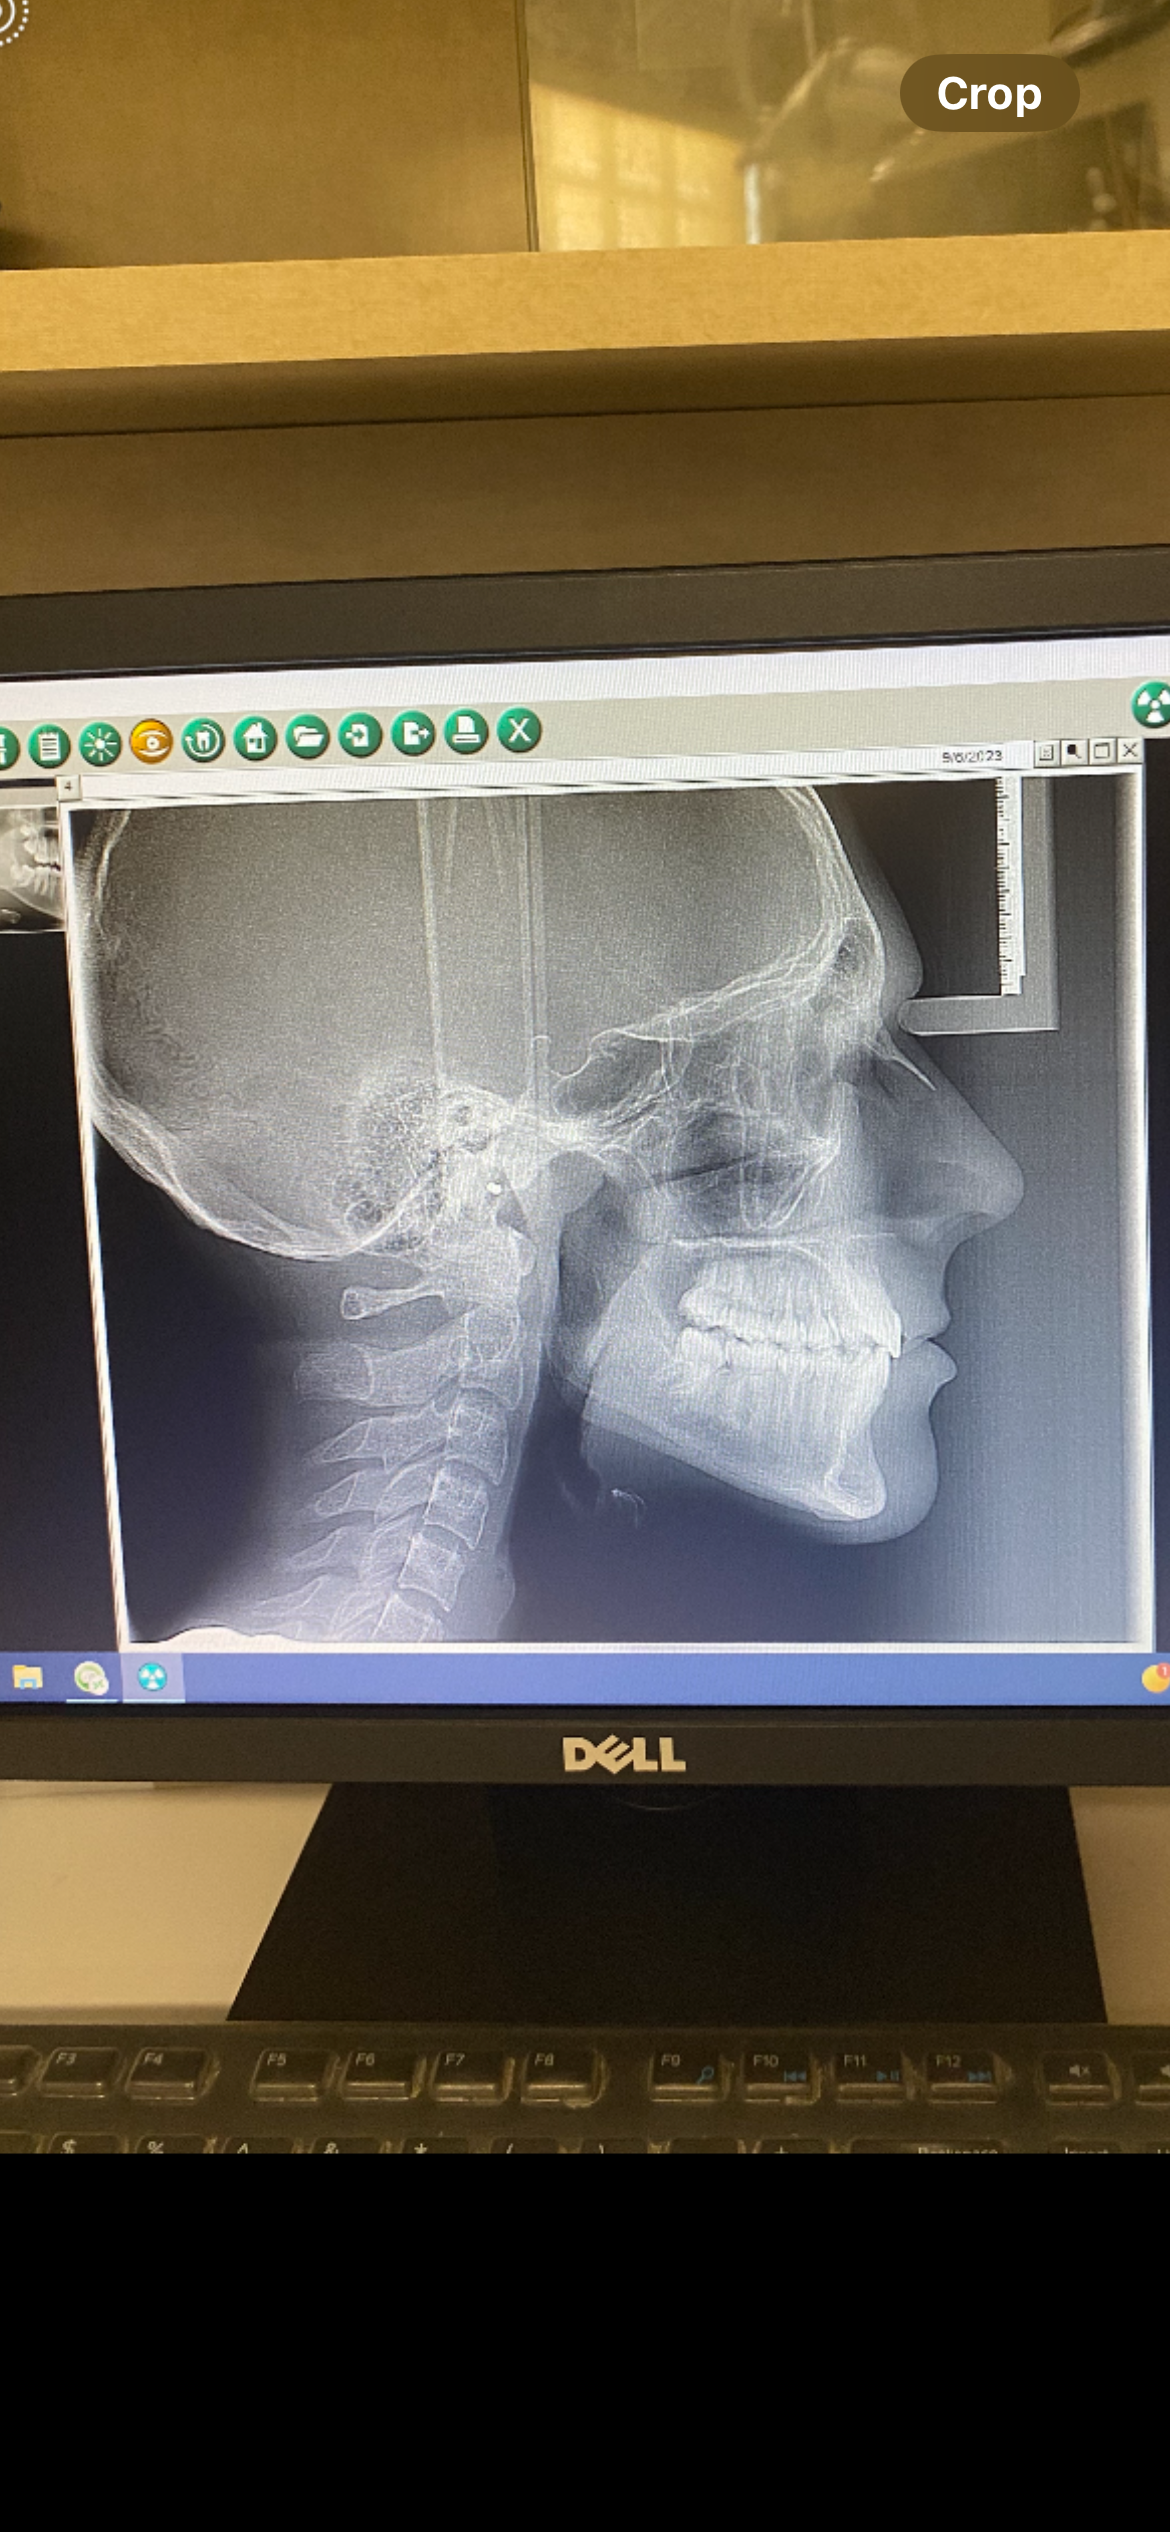

Found this pic from abt 2 years ago when I had first gotten braces im not sure if my maxilla and mandible is recessed or not pls help